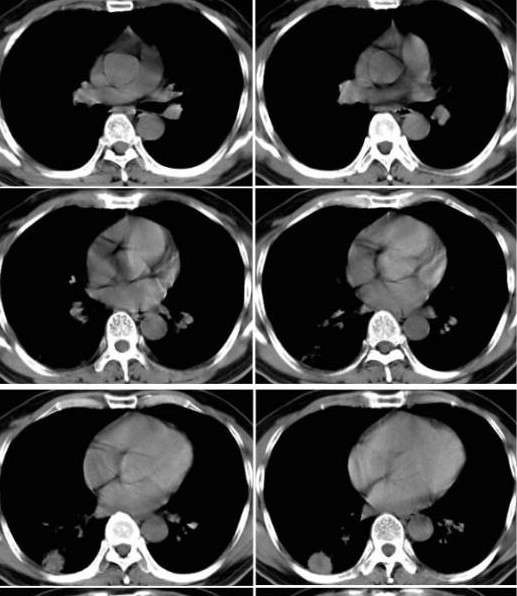

病例挑战:肺单发类圆形病变---球形肺炎

图6球形肺炎

公布结果:患者经抗感染治疗5天后复查ct,阴影基本消失,支持 球形肺炎!